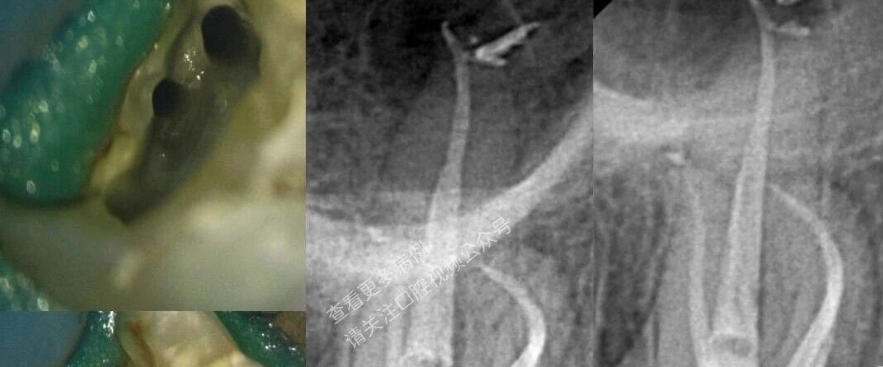

4、正常情况下,对于外伤露髓或意外穿髓的前牙可以将拔髓针插到牙根三分之二以下,尽量接近根尖孔,旋转180度将牙髓拔出。对于根管特别粗大的前牙,还可以考虑 双针术拔髓。

双针术

先用75%的酒精消毒洞口及根管口,参照牙根实际长度,先用光滑髓针,沿远中根管侧壁,慢慢插入根尖1/3部,稍加晃动,使牙髓与根管壁稍有分离,给倒钩髓针造一通路。同法在近中制造通路,然后用两根倒钩髓针在近远中沿通路插至根尖1/3部,中途如有阻力,不可勉强深入,两针柄交叉同时旋转180°,钩住根髓拔除。操作时避免粗暴动作,以免断于根管内,不易取出。

双针术在临床实践中能够较好的固定牙髓组织,完整拔除牙髓组织的成功率更高,避免将牙髓组织撕碎造成拔髓不全,不失为值得推广的一种好方法。